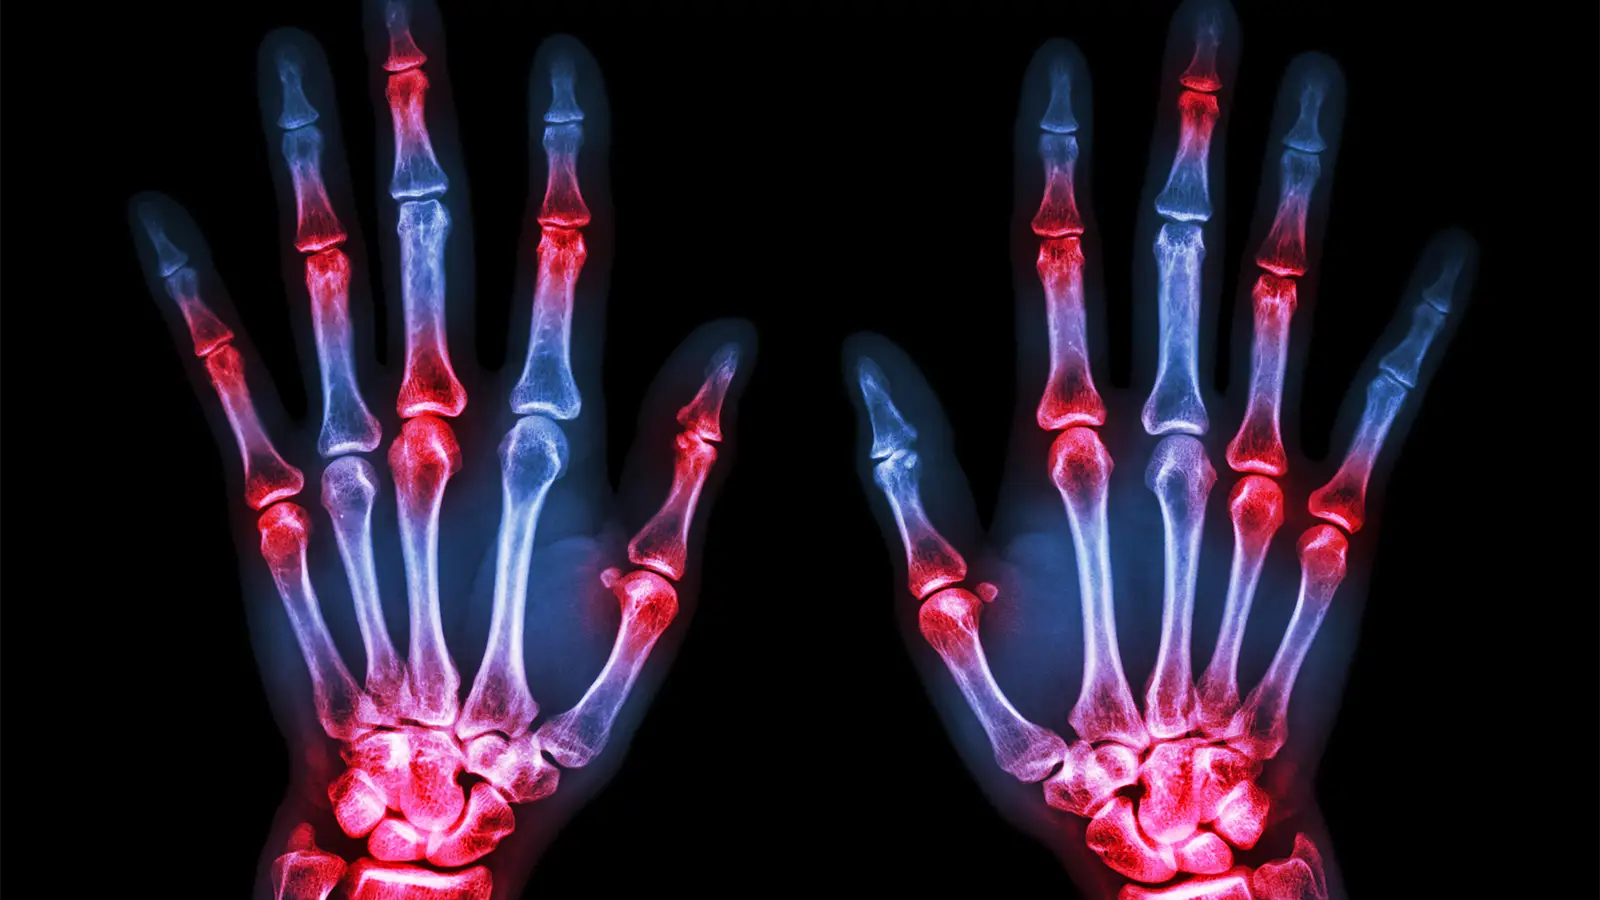

- The Sharp/van der Heijde (SvdH) method for analyzing X-ray images is the standard way to measure joint space narrowing and bone erosions in rheumatoid arthritis, requiring well-trained readers.

A machine-learning system for analyzing rheumatoid arthritis (RA) patients’ X-rays was able to produce Sharp/van der Heijde (SvdH) scores, the standard way to quantify joint space narrowing and bone erosions, with good accuracy when compared with human readers, researchers said.